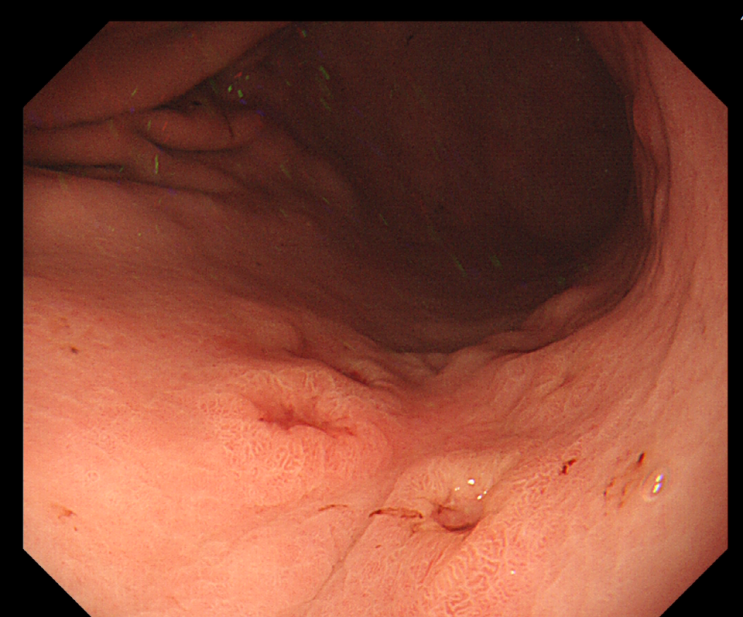

[왕십리 위암검진] 서울으뜸내과, 검진으로 발견된 위암(반지세포암)

#서울으뜸내과 #왕십리위암검진 #왕십리국가검진 #왕십리내과 #왕십리암검진 #신당동암검진 #신당역위내시...